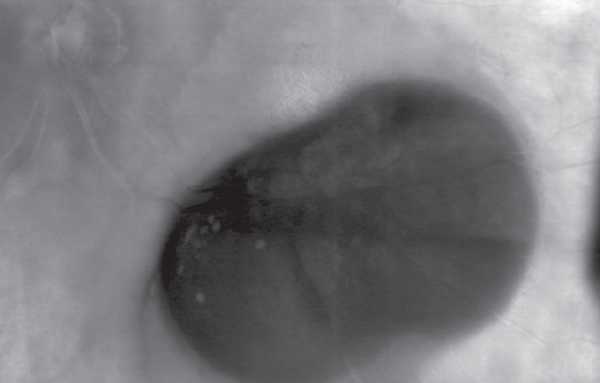

По данным инфракрасной сканирующей лазерной офтальмоскопии в ретро-режиме определялось округлое объёмное образование, полностью блокирующее сигнал от глубжележащей склеры. В отличие от новообразований сосудистой оболочки эта зона имела чёткие контуры, характерные для геморрагической отслойки пигментного эпителия сетчатки (рис. 4).

Рис. 4. Инфракрасная сканирующая лазерная офтальмоскопия в ретро-режиме. Изображение округлого объёмного образования

Fig. 4. Image of infrared scanning laser ophthalmoscopy in retro mode shows a round mass